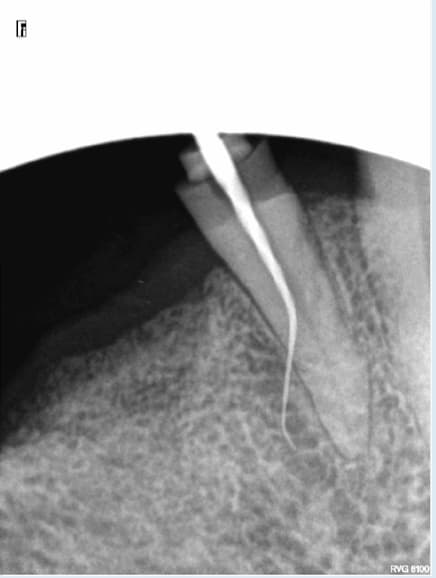

J'y comprend rien, première fois que ca m'arrive. Sans forcer au SX. S1 en localisation d'apex BIp BIp BIp !

Un gros canal latéral ? Un peu hardcore le s1 pour une cathétérisation.